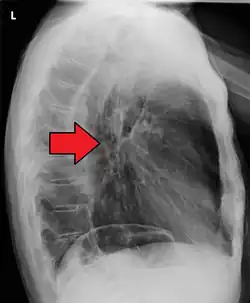

Although an occlusive tumor may be suspected on a barium swallow or barium meal, the diagnosis is best made with an examination using an endoscope. This involves the passing of a flexible tube with a light and camera down the esophagus and examining the wall, and is called an esophagogastroduodenoscopy. Biopsies taken of suspicious lesions are then examined histologically for signs of malignancy.

Additional testing is needed to assess how much the cancer has spread (see § Staging, below). Computed tomography (CT) of the chest, abdomen and pelvis can evaluate whether the cancer has spread to adjacent tissues or distant organs (especially liver and lymph nodes). The sensitivity of a CT scan is limited by its ability to detect masses (e.g. enlarged lymph nodes or involved organs) generally larger than 1 cm.[44][45] Positron emission tomography is also used to estimate the extent of the disease and is regarded as more precise than CT alone.[46] PET/MR as a novel modality has shown promising results in preoperative staging with fair feasibility and good correlation in comparison to PET/CT. It can enhance tissue differentiation with lowering the radiation dose to the patient.[47] Esophageal endoscopic ultrasound can provide staging information regarding the level of tumor invasion, and possible spread to regional lymph nodes.